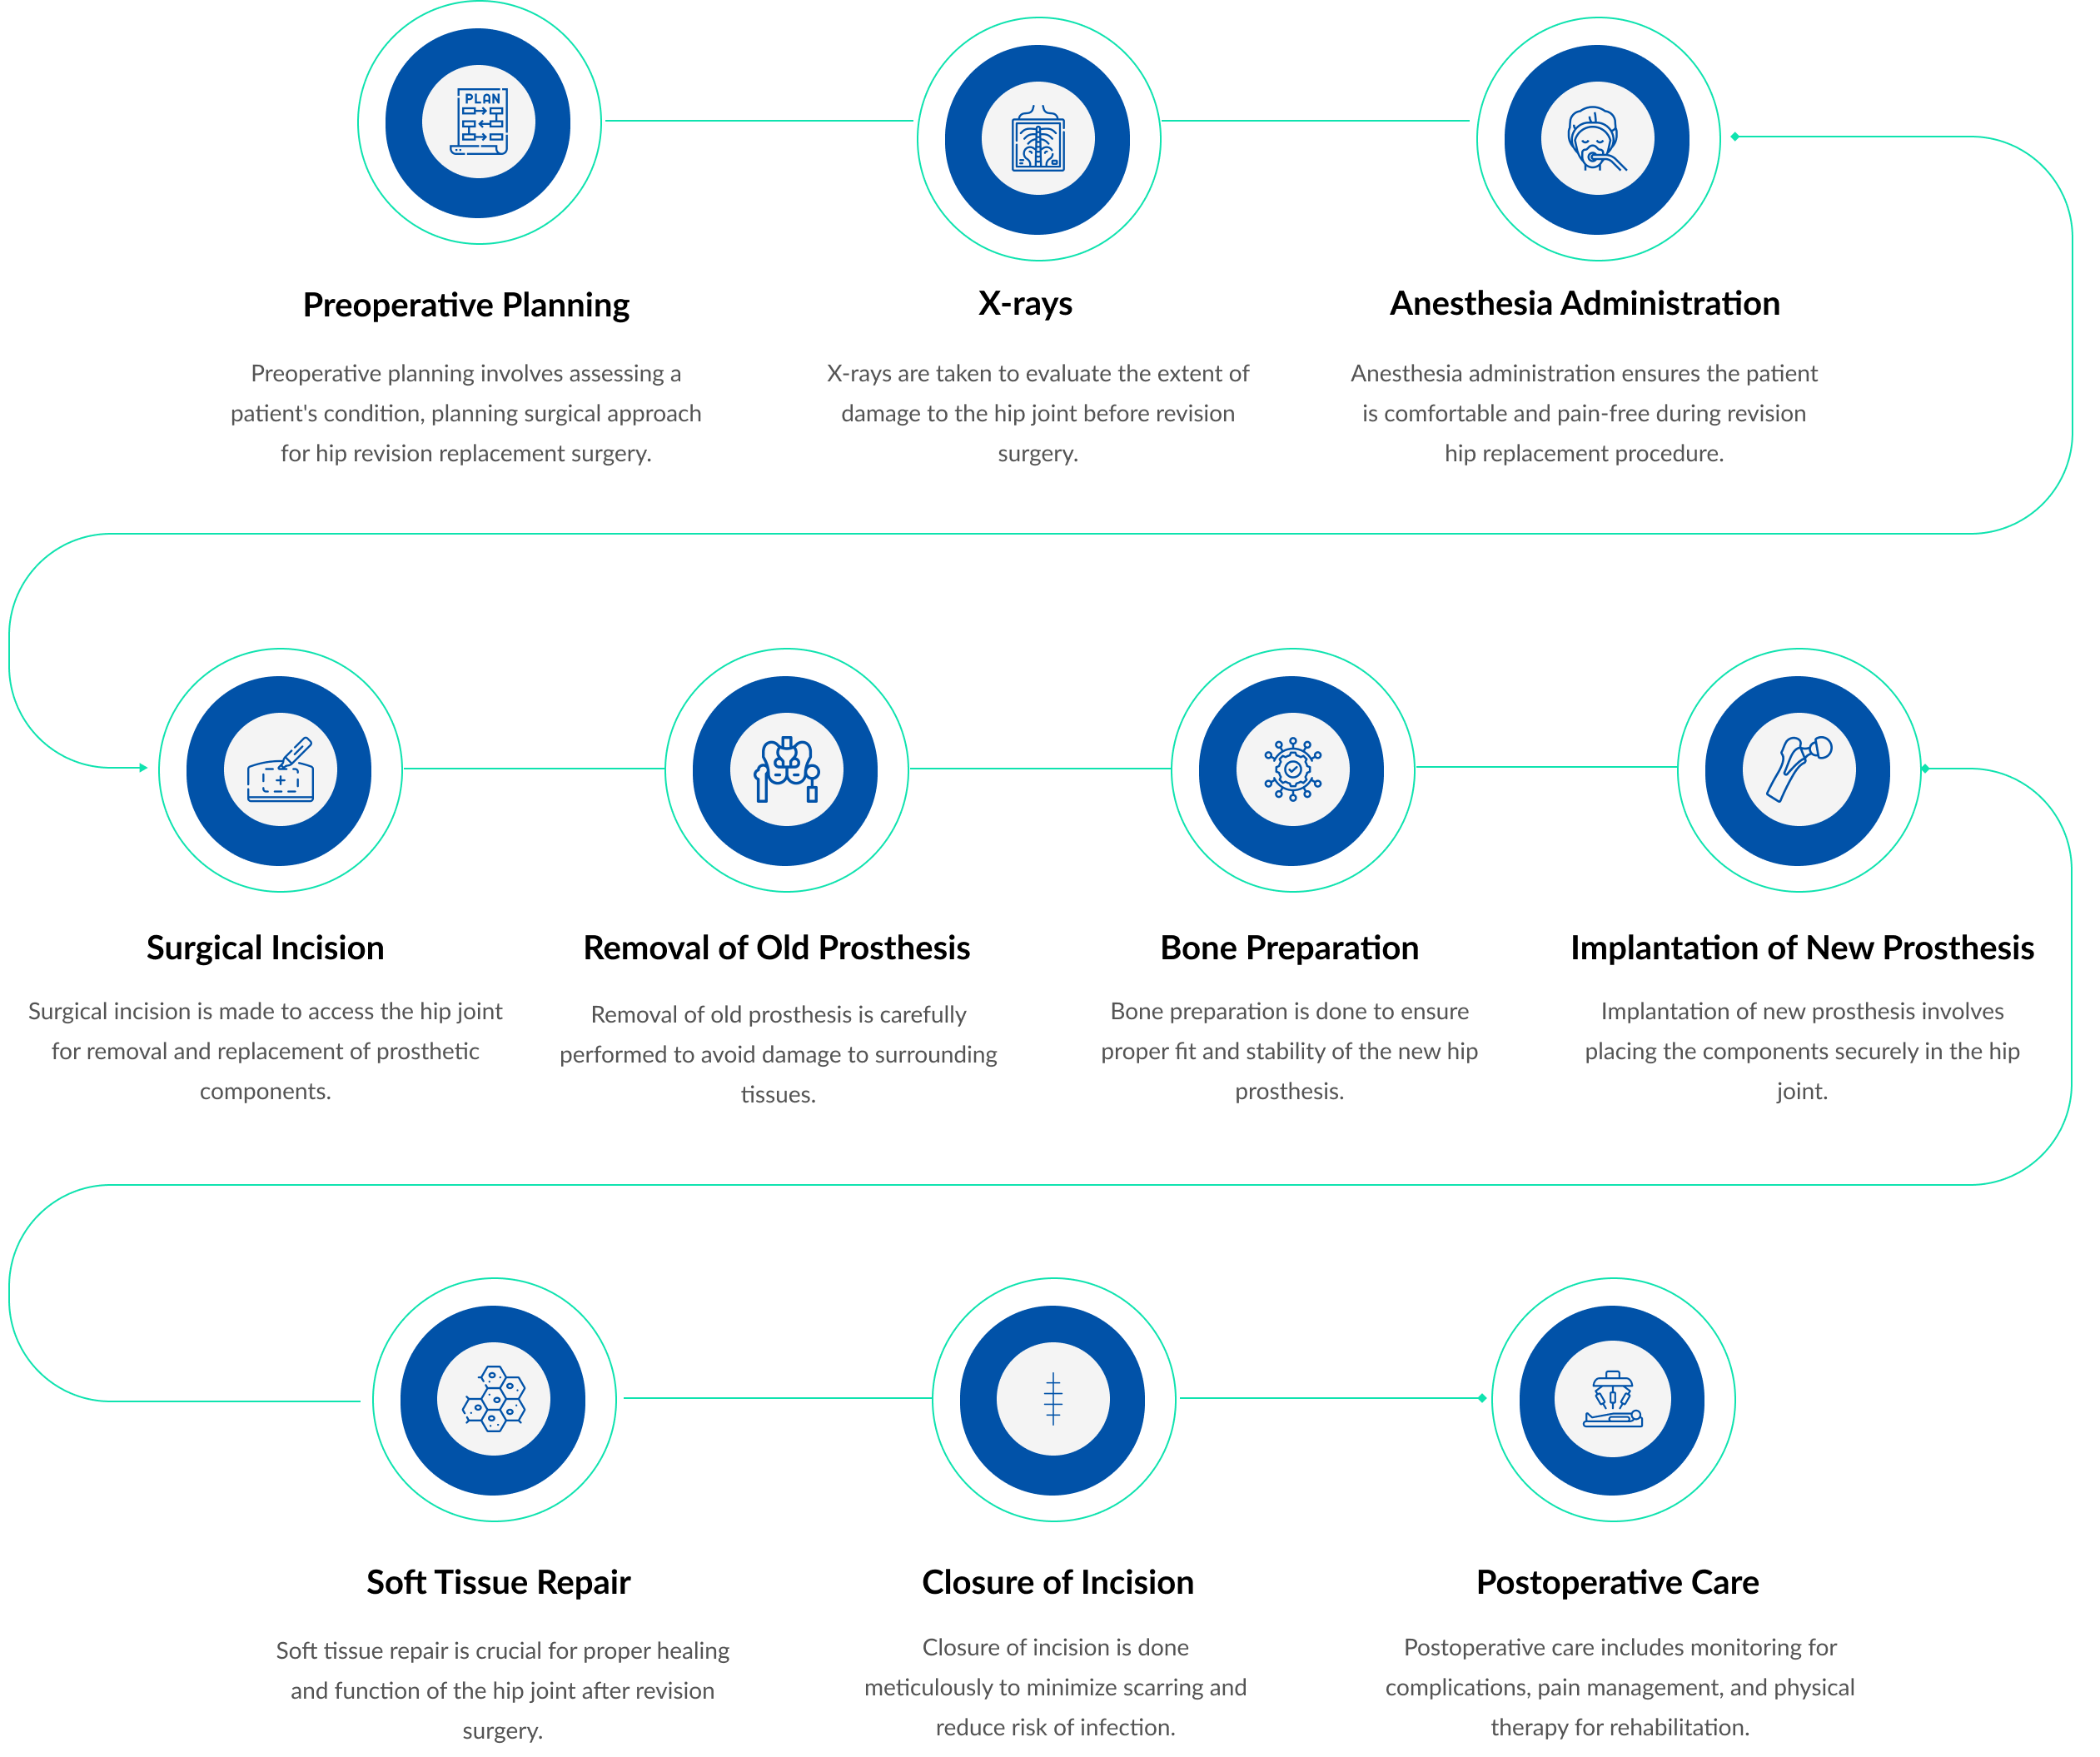

PROCEDURE

A hip revision operation involves removing and replacing a previously implanted hip prosthesis that has failed, typically due to wear, loosening, infection, or dislocation.